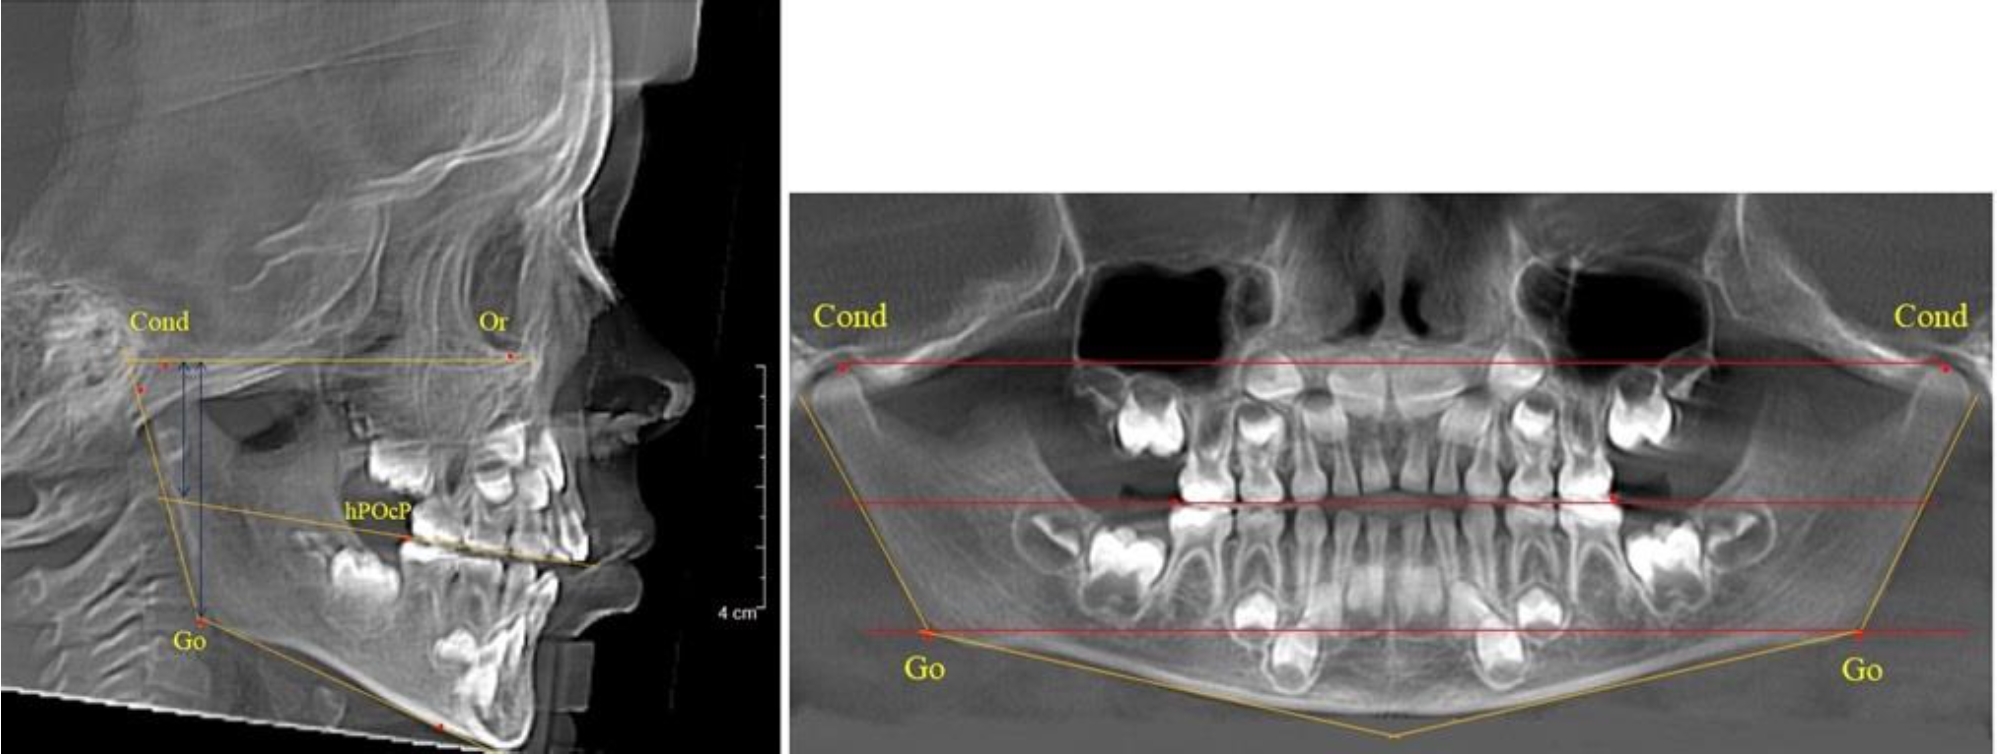

В 4-й группе были проанализированы 12 комплектов рентгенограмм, что составило (11,32 ± 3,08) % от общего числа. На всех рентгенограммах произошла полная смена всех молочных зубов постоянными. Окклюзионная линия делила ветвь на два отдела (рис. 4).

Рис. 4. ТРГ пациента после смены всех молочных резцов

Высота ветви у детей 4-й группы составляла (54,27 ± 2,59) мм, что было достоверно больше, чем у детей 1-й группы (р ˂ 0,05). При этом высота верхней окклюзионно-суставной части была (32,51 ± 1,72) мм, а нижней – (21,76 ± 1,42) мм. Высота верхней части была больше нижней, что и определяло особенности соразмерности частей ветви нижней челюсти в анализируемый возрастной период.

Относительные показатели соразмерности частей ветви нижней челюсти показали, что отношение высоты верхней части ветви к нижней в среднем составляло 1,49 ± 0,12. Отношение общей высоты ветви к верхней ее части составляло 1,67 ± 0,14, а отношение общей высоты ветви к нижней ее части было 2,49 ± 0,15, что и определяло особенности соразмерности частей ветви нижней челюсти в анализируемый возрастной период.